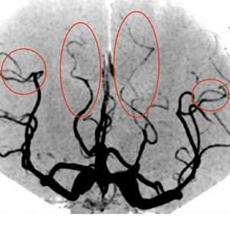

可逆性脳血管攣縮症候群(RCVS)という、脳血管の変化を伴う疾患があります。雷鳴頭痛といわれる急な頭痛で始まり、断続的に激しい痛みを繰り返す疾患です。MRA検査で血管攣縮(血管が縮む現象)を見つける事で診断が付きます。この血管攣縮の場所は、血管の先端部から始まり次第に中心部へ移動するとされているため、初期段階では先端部の細い血管の変化が見えにくい場合があります。

可逆性脳血管攣縮症候群の症例

このように、末梢動脈に焦点を当てた撮像チューニングを行う事で、発症早期の可逆性脳血管攣縮症候群(RCVS)が診断できます。